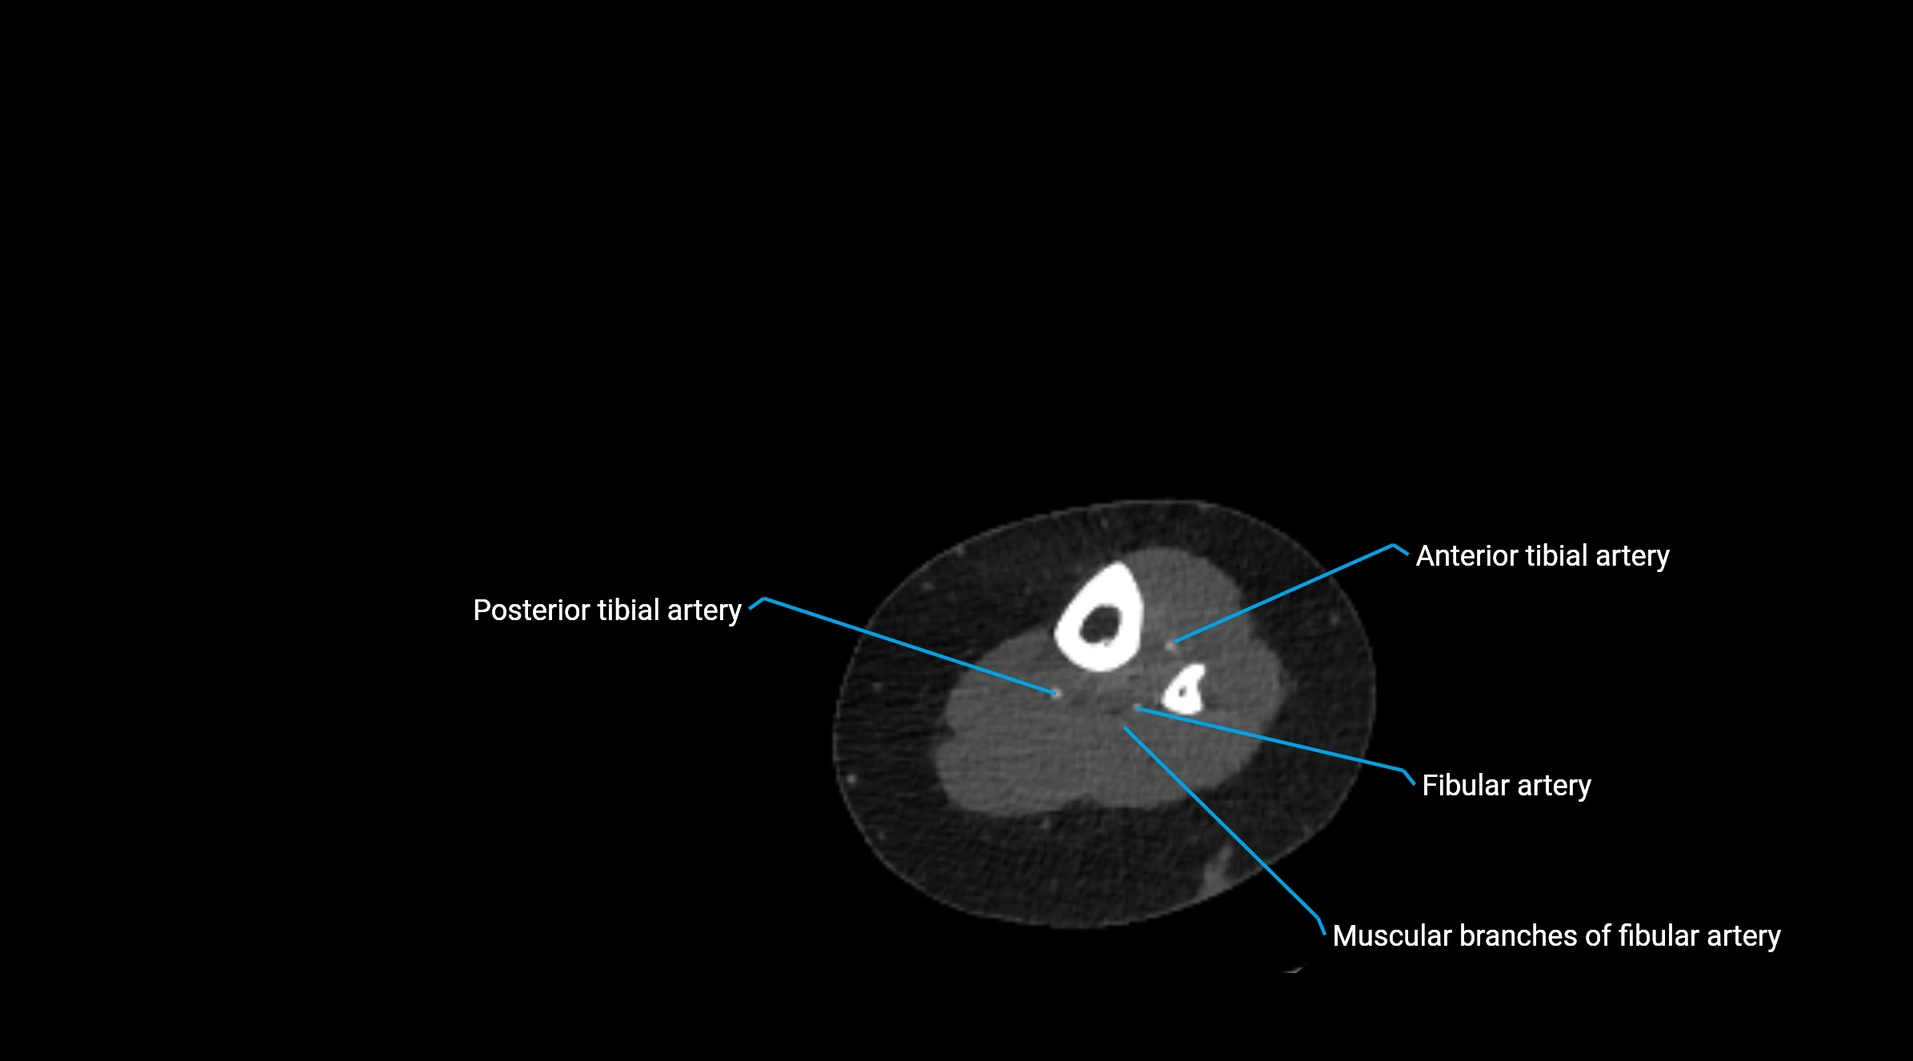

CT images

image